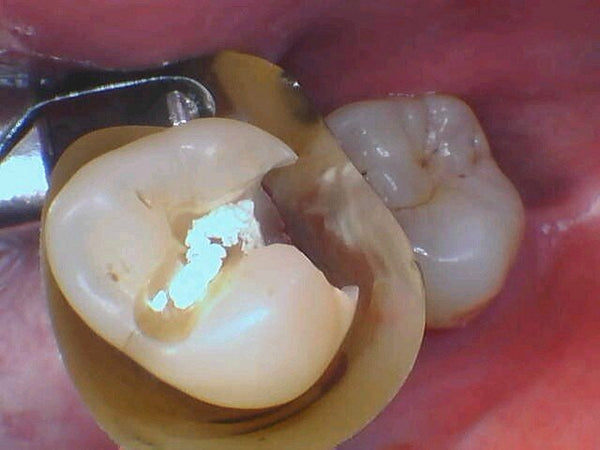

Direct composite crown replacing fractured Lithium Disilicate crown - With 8 month follow up

Introduction: Two factors set up this lithium disilicate crown for fracture: 1) Endo asscess weakened it. 2) Occlusal thickness not adequate. Crown has fractured Distal half of lithium disilicate crown has... Read More